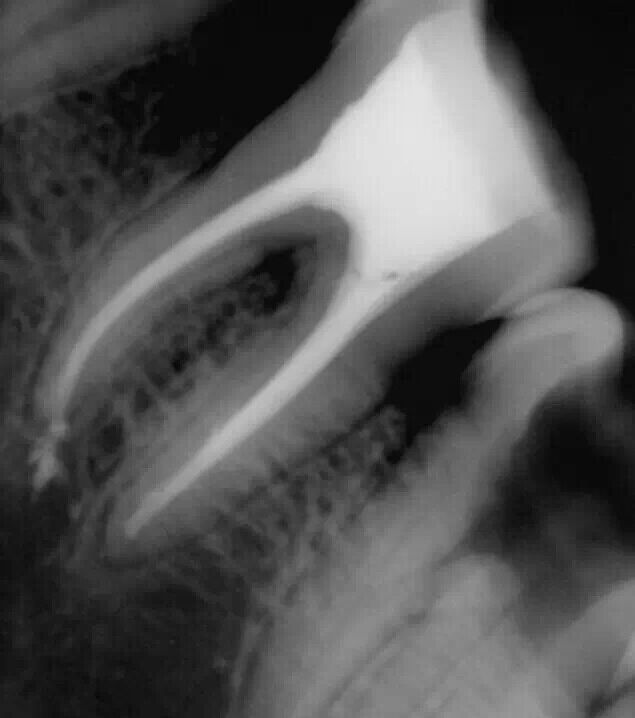

震出一半時(shí)照的X片